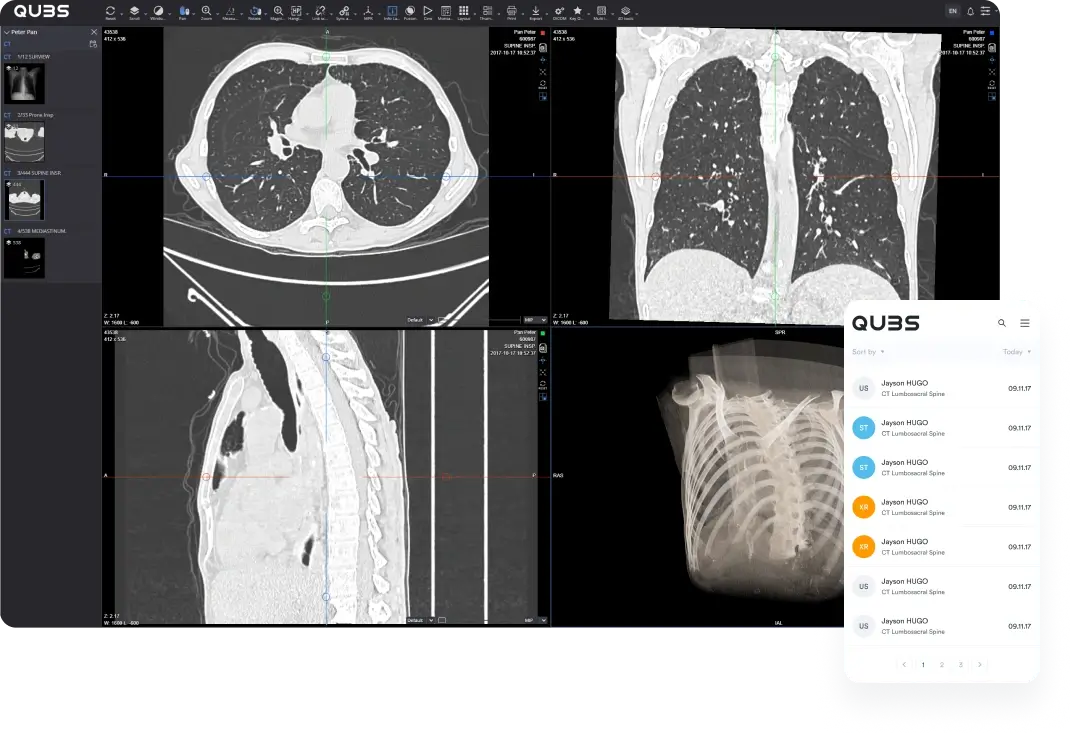

Comprehensive toolkit

Our online portal furnishes all essential tools, from precise measurements to the ability to download full DICOM data for seamless import into their preferred software.

DICOM file accessibility

Allow specialists to download complete DICOM files effortlessly, facilitating easy imports into their respective software—ideal for procedures like orthodontics.